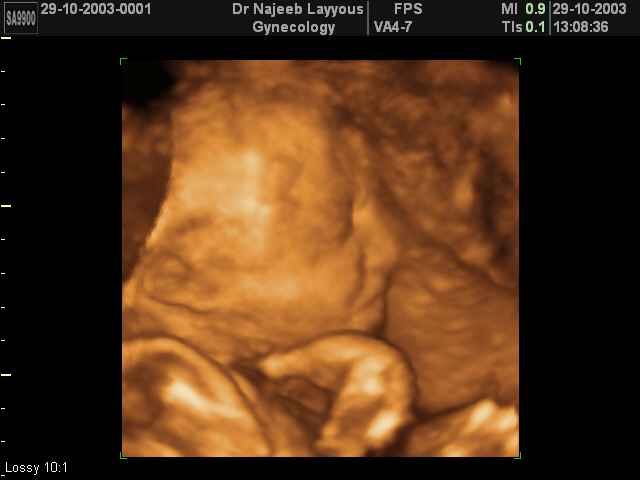

- صور جانبية لرأس الجنين

صور جانبية لرأس الجنين بجهاز الالتراساوند ثلاثي الأبعاد | الدكتور نجيب ليوس